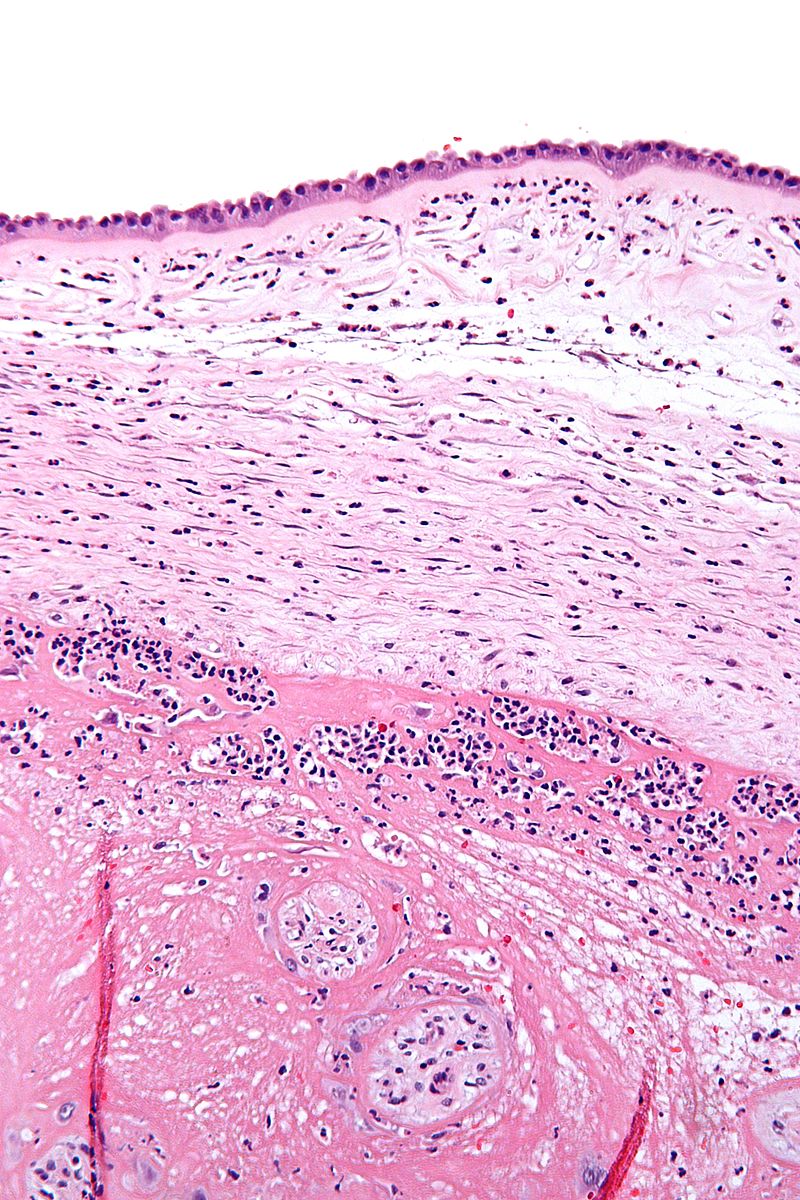

Chorioamnionitis

Cluster of blue dots are neutrophils, eosinophils, and lymphocytes (due to the inflammatory response in the amniotic membranes

Cluster of blue dots are neutrophils, eosinophils, and lymphocytes (due to the inflammatory response in the amniotic membranes